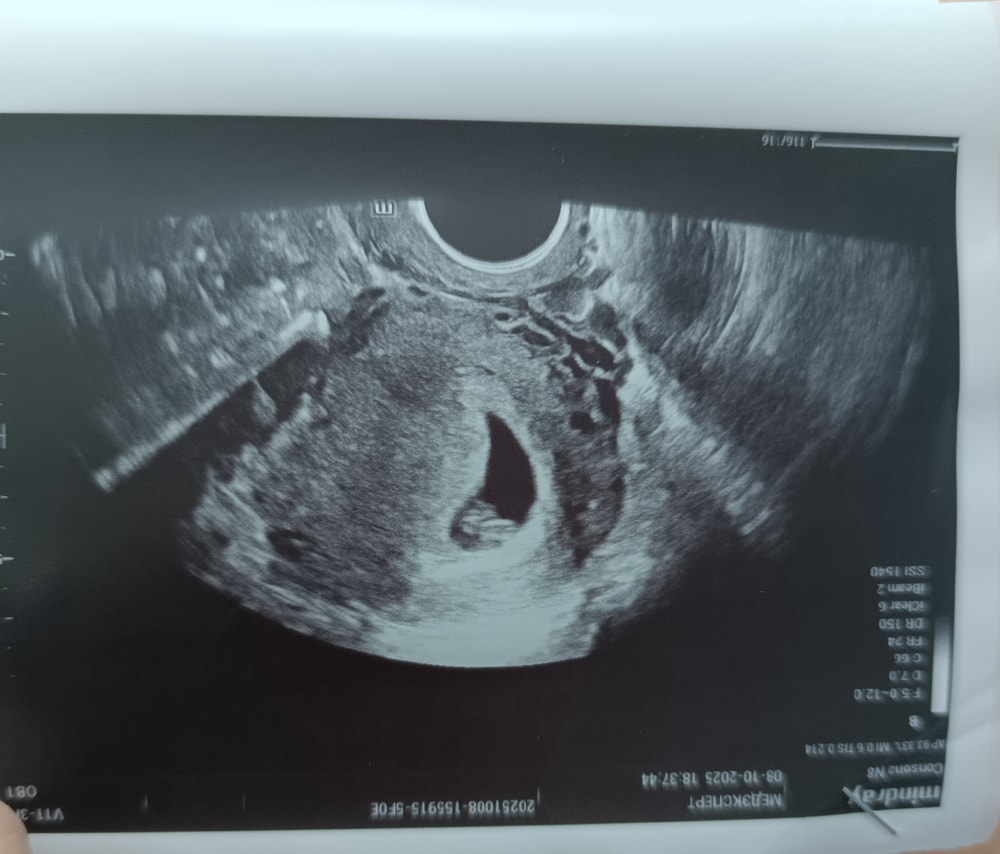

Почти тоже самое в 6 нед 5 дней

Похоже на тонус верхней стенки матки , но такое может быть как только датчик вводят в матку ....